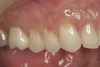

Just as it is important to recognize the signs of instability during an examination, it is equally important to recognize the signs of stability. A patient may exhibit numerous signs of stability and only a few signs of instability or vice versa. The signs of stability are even, stable holding contacts on all teeth with the joints in centric relation (Figure 2), anterior guidance that immediately discludes the posterior teeth in excursive and protrusive movements, stable bilateral temporomandibular joints, and teeth in harmony with the neutral zone.6 By knowing the signs of stability, they can be incorporated into future restorative treatment.

Figure 2  CENTRIC RELATION Stable, even holding contacts on all teeth when the condyles are in CR is a primary sign of occlusal stability.

Figure 2